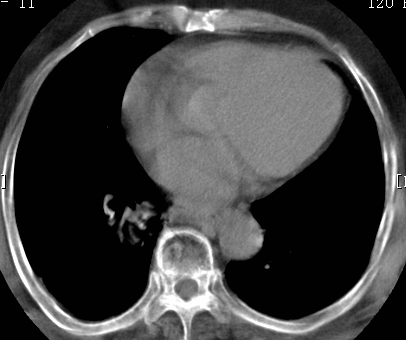

标题: CT26680:肺部右下肺静脉干结节的界定 [打印本页]

标题: CT26680:肺部右下肺静脉干结节的界定

增强适应症